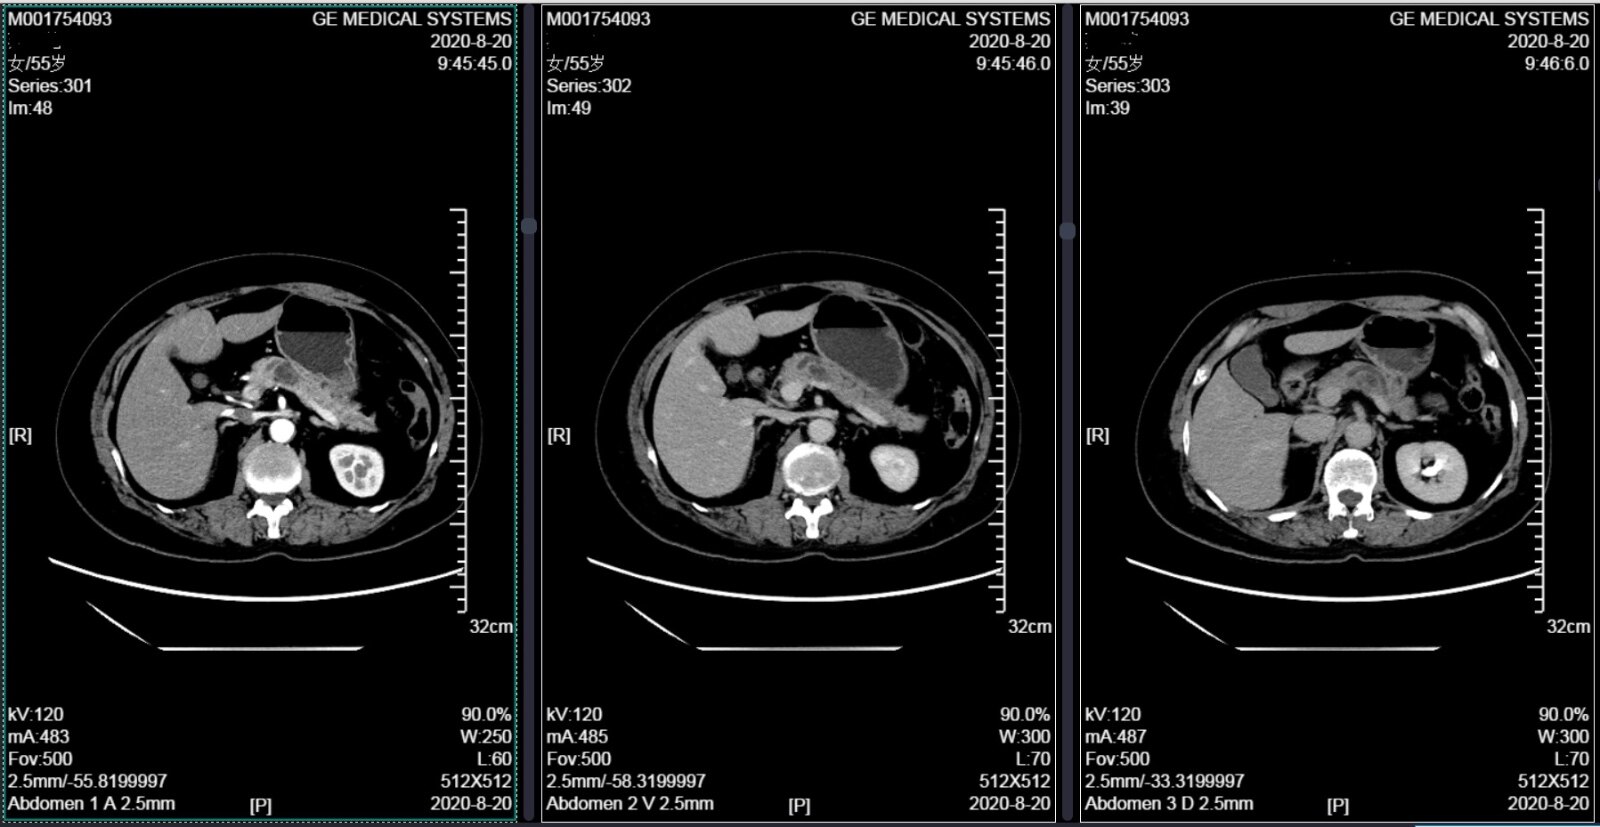

2、患者于2年前查体发现胰腺囊肿,未予诊治,2月前体检复查行腹部CT示:胰管扩张,胰体部稍低密度灶导管内乳头状粘液瘤?患者自诉无不适,无腹痛、腹胀、恶心、呕吐、黄疸、头晕、乏力,无发热,无尿频、尿急、尿痛。1月后行上腹部增强MRI+MRCP示:胰管扩张,胰体部多房囊性灶,IPMN可能性大。为行进一步诊治收入院,患者自起病来,精神状态良好,体力情况良好,睡眠食欲良好,体重无明显变化,大小便正常;

4、外院腹部增强MRI+MRCP:胰管扩张,胰体部多房囊性灶,胰腺导管内乳头状黏液性肿瘤可能性大;肝内多发囊肿;左侧肾上腺结节样增粗,小腺瘤可能。

CT和核磁都发现囊肿与主胰管相通,并且发现主胰管扩张、在胰腺体尾部多发囊肿,提示胰腺体尾部多发病变。同时疾病较2年前进展,说明胰腺导管内乳头状黏液性肿瘤在慢慢的发生改变,有必要在癌变前手术,切除胰腺体尾部,阻止癌变。同时目前肿瘤偏良性,希望能够尽量保留住脾脏,减少术后血栓、免疫功能受损等等影响。

我们重建胰腺后,发现肿瘤与脾脏动脉、脾静脉有间隔,可以切除胰体尾、同时保留脾脏血管,保证脾脏安全。于是我们为患者实施了微创腹腔镜保留脾脏的胰体尾切除手术。术后患者恢复顺利,由于是微创手术,腹部仅仅有5个手指粗的瘢痕,术后疼痛轻、恢复快,术后10天就顺利出院。